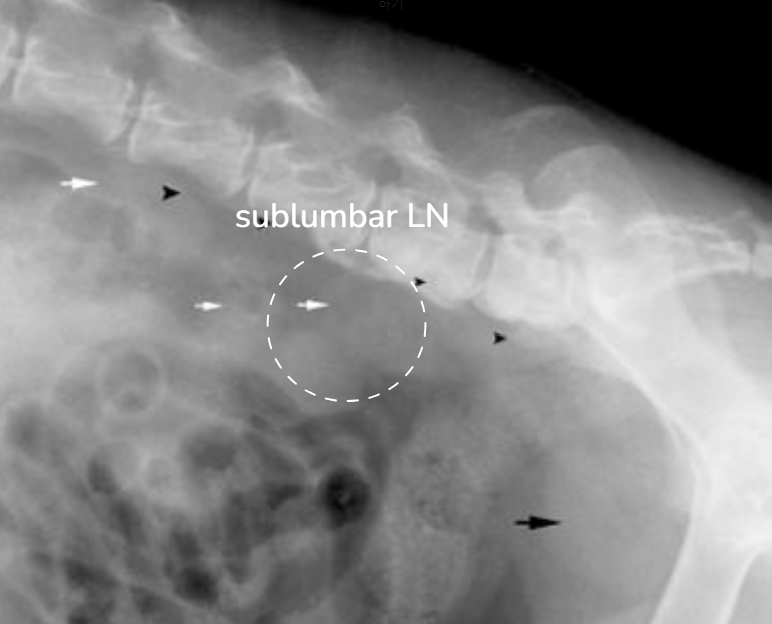

| Radiographs | |

![]() | ![]() |

| X-ray ์๊ฒฌ | ์์ธ |

|---|---|

| trachea์ dorsal variation | Mediastinal, hilar lymphadenomegaly |

| Sternal LN ์ดฌ์๋จ | Sternal lymphadenomegaly : MGT๊ฐ sternal ์ชฝ์ผ๋ก๋ ์ ์ด |

| descending colon์ ventral variation | Sublumbar lymphadenomegaly (์์ถํ ์ชฝ LN ๋น๋) |

| ์ฅ ์ชฝ์์ mass effect ์์์ ํฐ ๋ฉ์ด๋ฆฌ๊ฐ ์ดฌ์๋จ | Mesenteric lymphadenopathy (์ฅ๊ฐ๋ง ์ชฝ LN ๋น๋) |